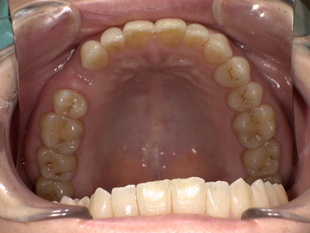

■ 【Before→After】ノンクラスプ義歯で口元の印象が大きく若返り

▼ 治療前

-

歯の欠損部の影響で口元がへこみ、老けた印象

バネ式の入れ歯では金具が見えてしまう

噛み合わせが不安定で、しっかり食べられない